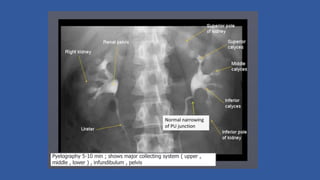

5- minute film

• 5 minute film shows nephrogram, renal pelvis, upper part of ureter

• Compression band is now applied on patient's abdomen and the

balloon is positioned on anterior superior iliac spine where ureters

cross pelvic brim. This is to produce better pelvicalyceal distension

• Compression inhibits ureteric drainage and promotes distension of

pelvicalyceal system, optimizing their visualization

5-min film

BEFORE COMPRESSION AFTER COMPRESSION